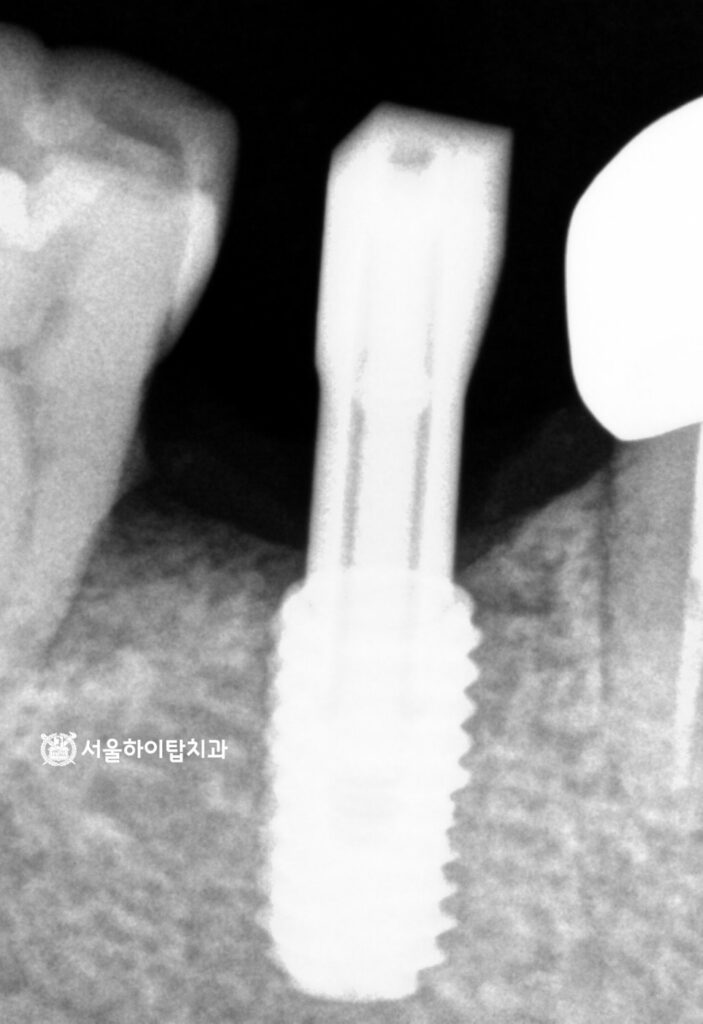

시뮬레이션 데이터에 따라

정확한 위치에 안정하게

픽스처가 심겨진 모습입니다.

당일 식립이 이루어졌기 때문에,

한 번의 시술로 기능을 회복할 수 있고,

치유 기간도 단축되어

빠른 회복이 기대됩니다.

또한, 장기간 상실된 부위와

치주염으로 인해 손상된 뼈를

동시에 관리할 수 있어,

교합 안정과 심미적 회복도

동시에 도모할 수 있습니다.